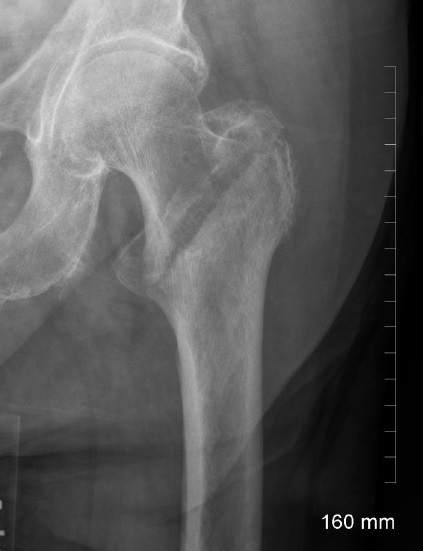

Identify

intertrochanteric fracture